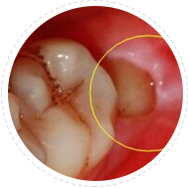

80%~90% 的口臭是来源于口腔局部疾患,口腔中有未治疗的深度龋齿、残根、残冠、不良修复体、牙髓坏死、牙龈炎、牙周炎等都可以引起口臭,如果不治疗则会引起:

树脂补牙即用无菌器械清除龋坏部分,清洗窝洞后用树脂材料进行填充,以恢复其外形和功能,对于严重的龋齿,需要进行根管治疗。

适应症:龋齿引起口臭